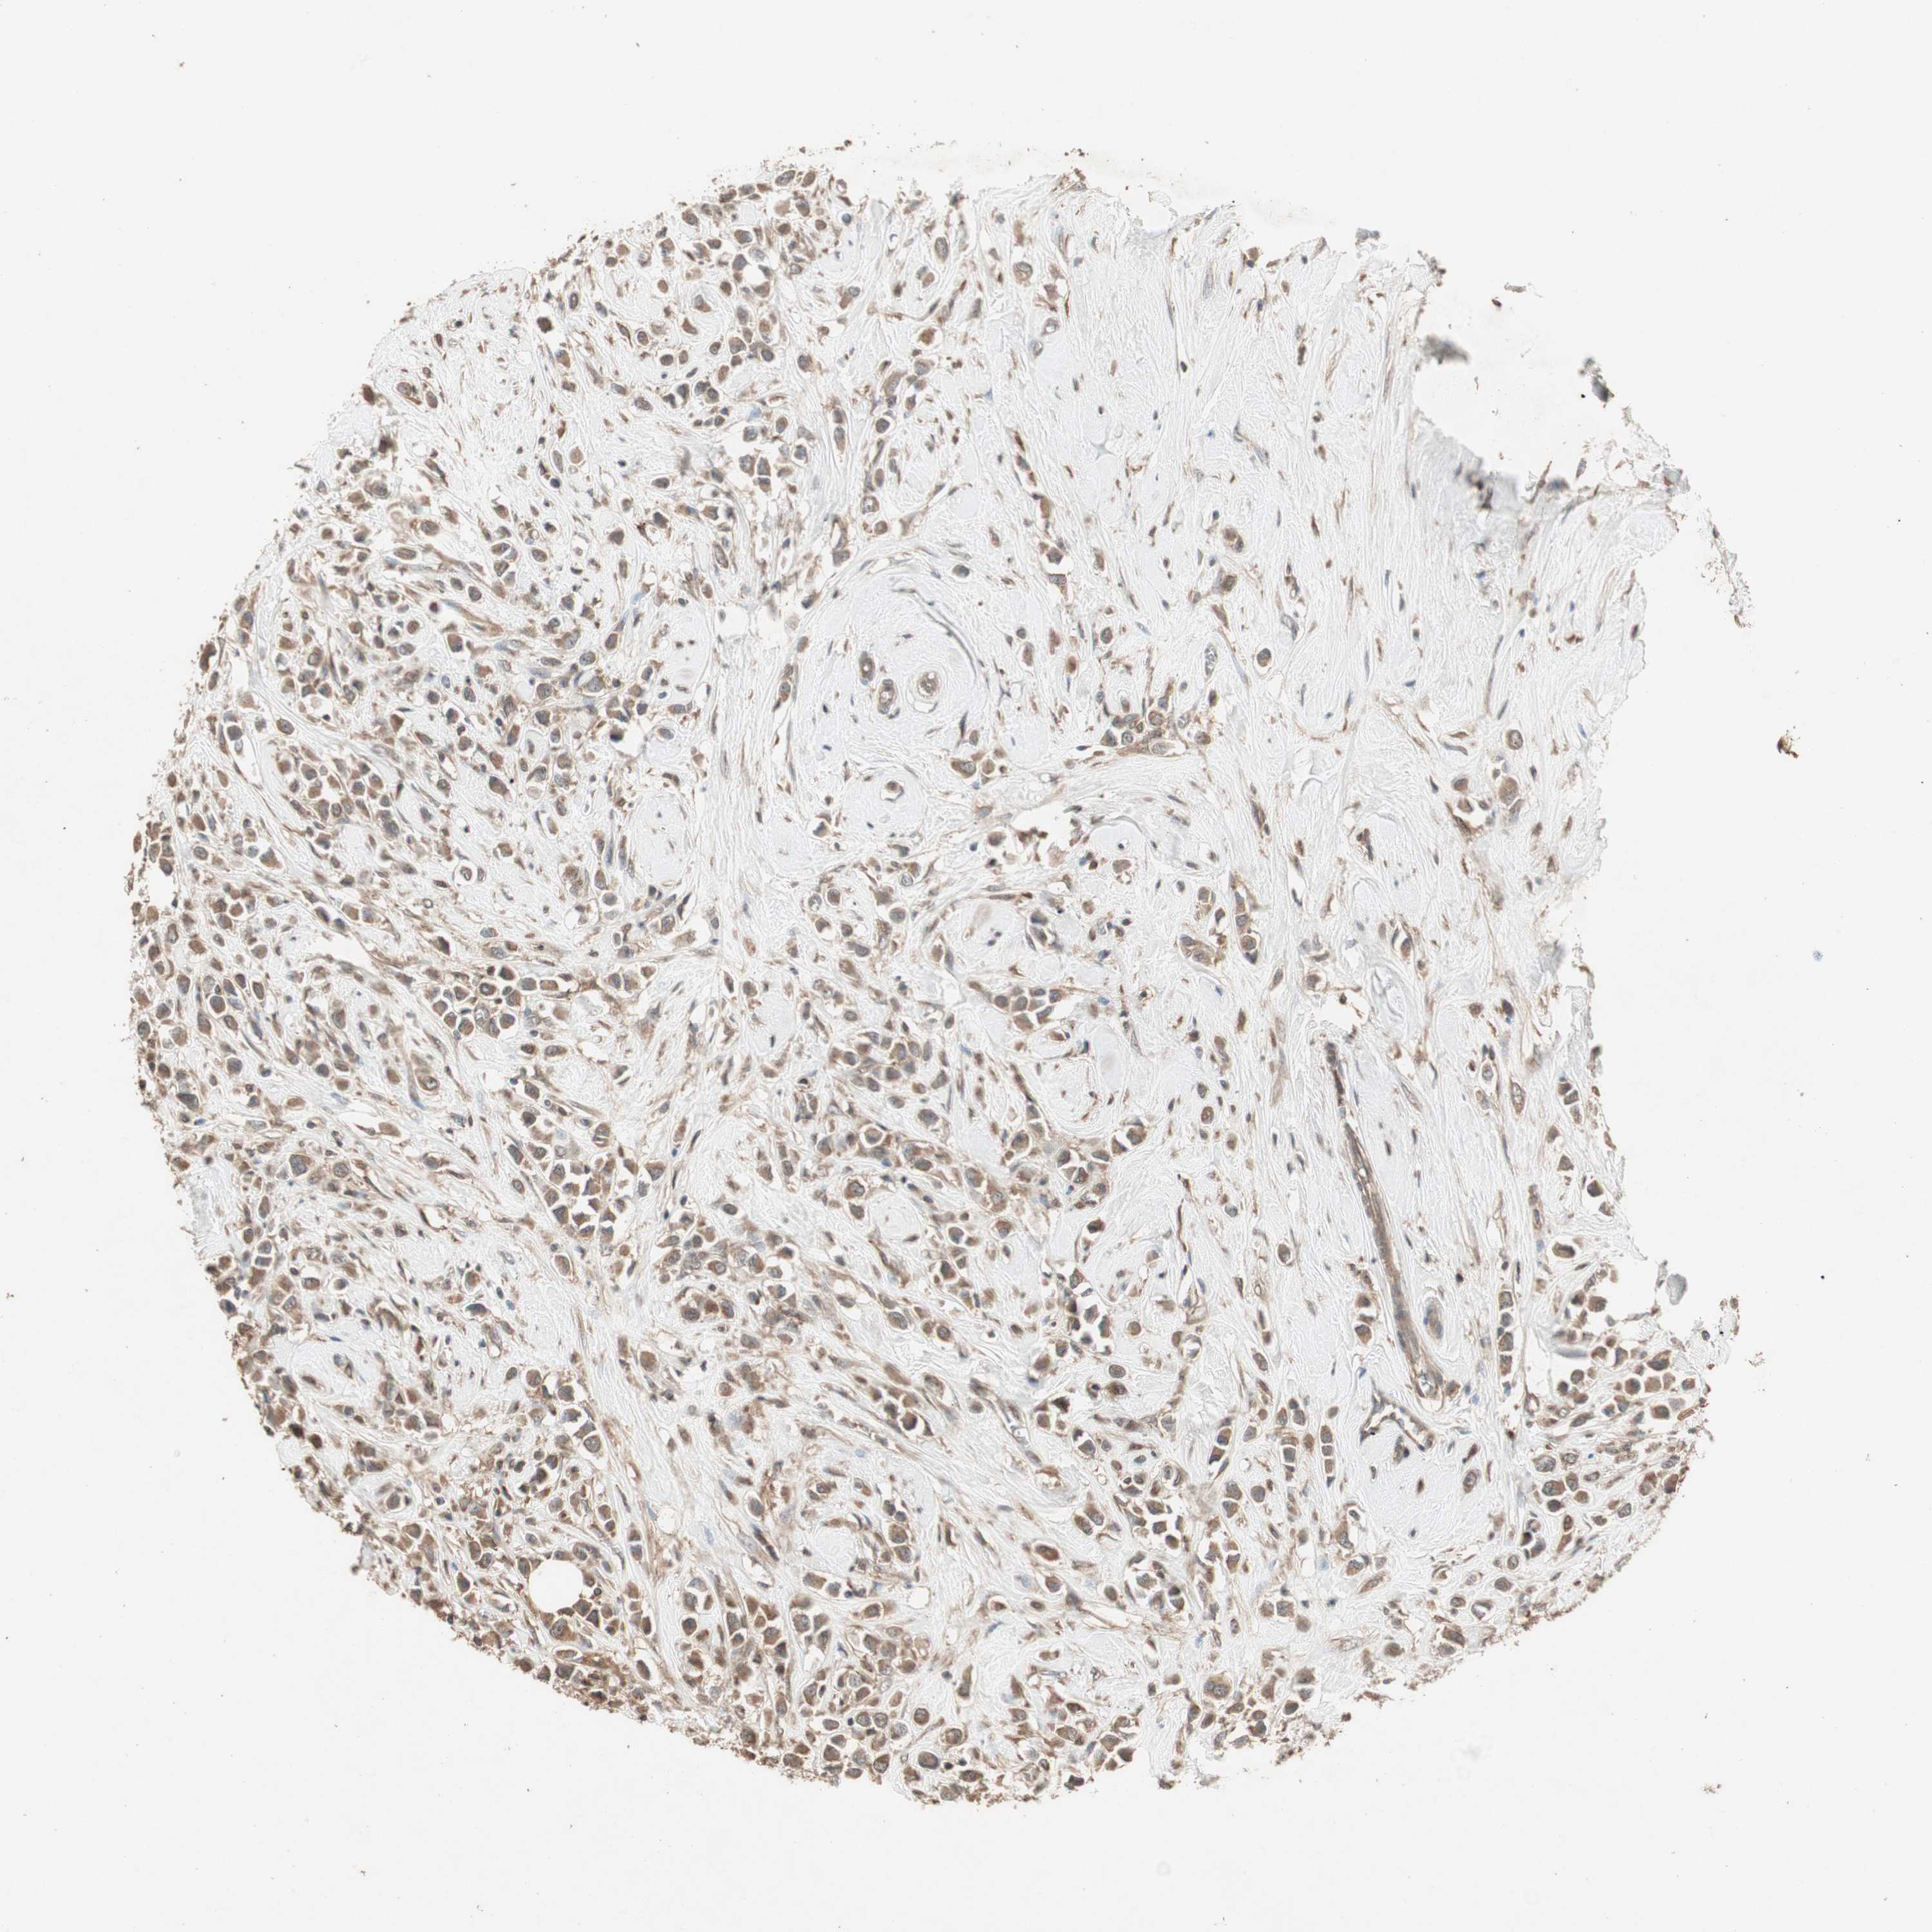

BRCA TCGA BRCA VALIDATION PROTEIN EXPRESSION